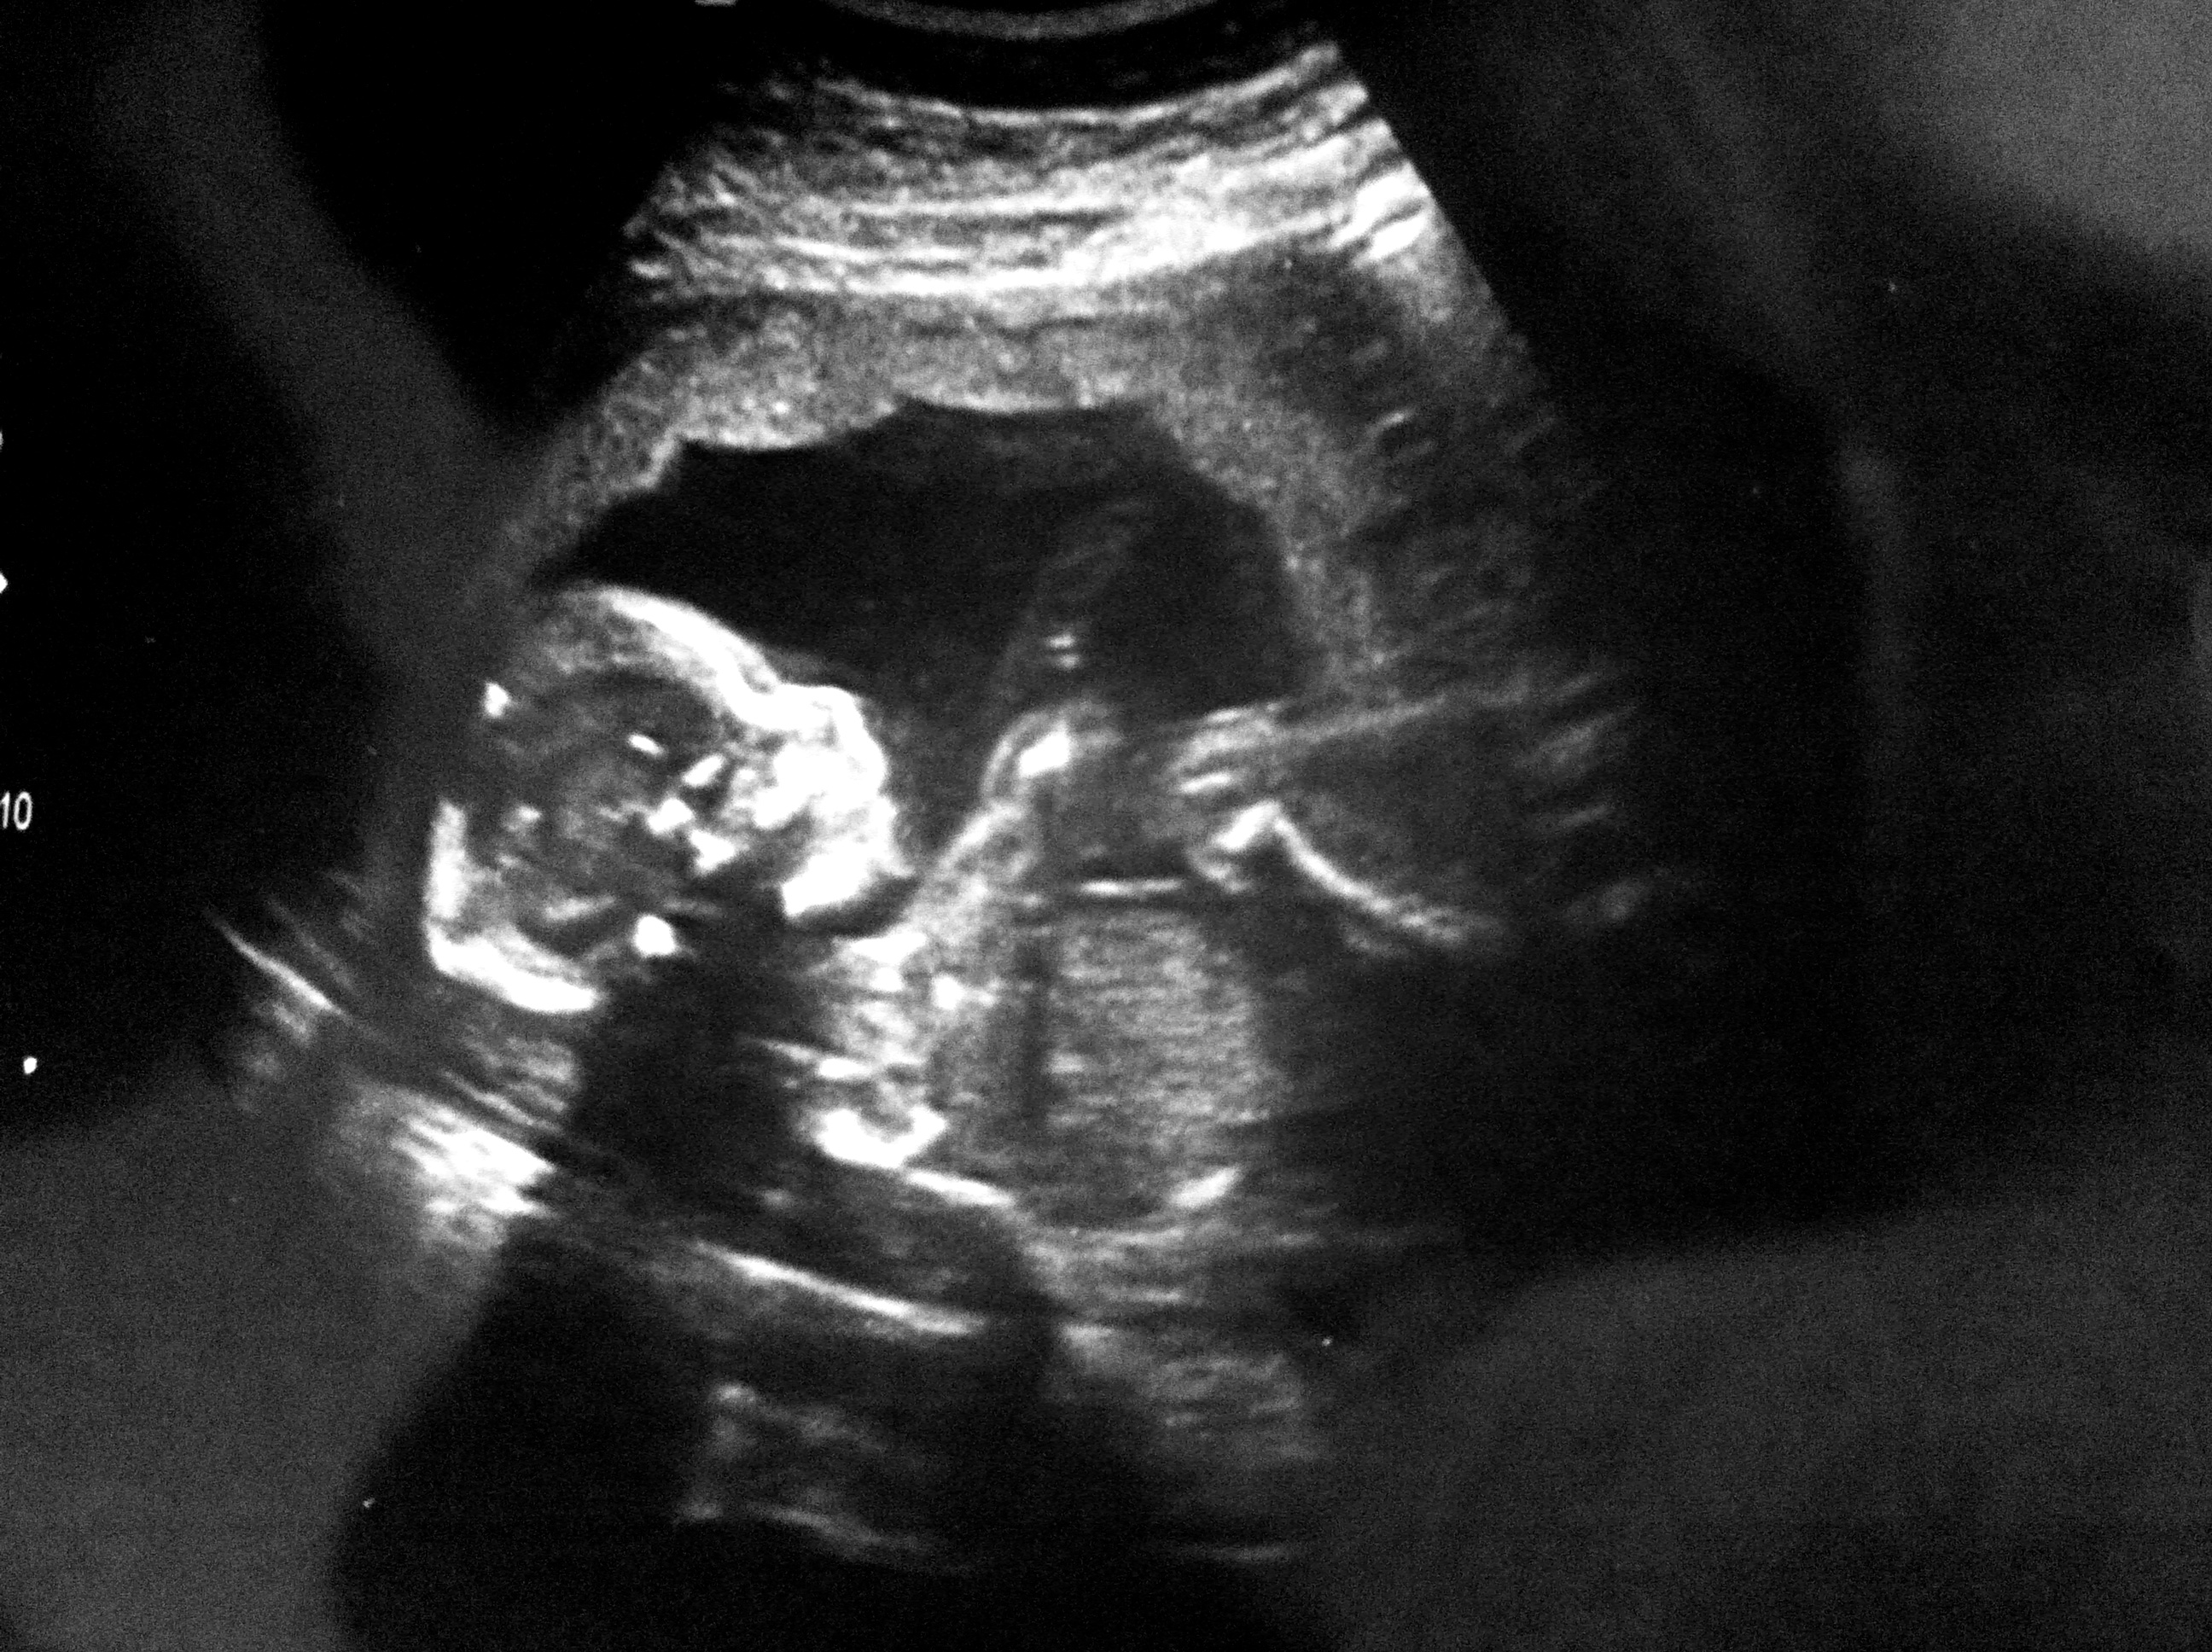

So there’s our name story. I hope Ritter Craig gets Eric’s musical talents and my drive and tenacity. What a combination that would be! I think he’ll be tall (he’s already measuring a little long). My dad and 1/2 brother are very tall, and Eric’s pretty tall. We already know from the ultrasound that he has my feet. And we know he will have blue eyes since it’s genetically impossible for two blue eyed people to have a brown or green eyed child. And since we both have fine/thin hair, he’ll probably get that curse too – unless a miracle happens and he ends up with my dad’s hair. It’s crazy all the little things we know about him already. And now that he has a name I feel even more connected to him than before. And feeling him kick and move now has made it even more exciting.